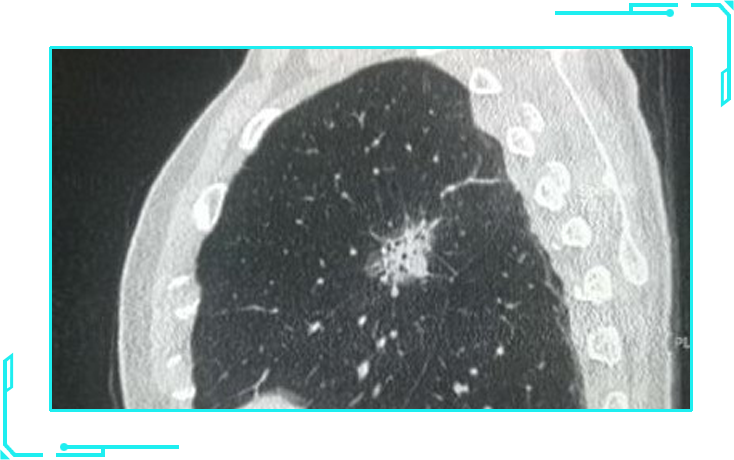

纯磨玻璃结节

纯磨玻璃结节,影像表现像磨砂玻璃一样,看起来影像比较虚。